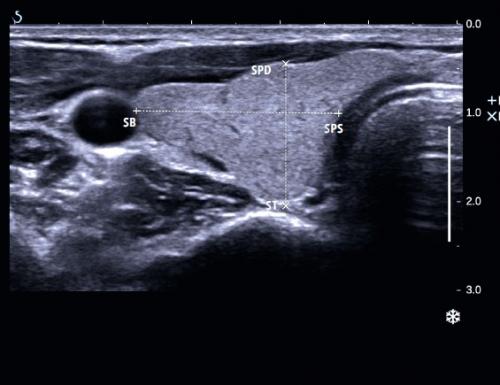

- Глубина доли щитовидной железы – это наибольшее расстояние между передней и задней поверхностями, измеренное по вертикали. Линии, обозначенные этими расстояниями, должны пересекаться приблизительно под прямым углом. Ширина и глубина доли измеряются в поперечной плоскости в месте, где эти размеры являются самыми большими, то есть обычно на высоте перешейка, в центрально-нижней части доли (рис. 4).

Правая доля щитовидной железы в поперечном сечении

Рис. 4. Правая доля щитовидной железы в поперечном сечении. Показано измерение двух размеров доли щитовидной железы: ширина (+) и глубина (×). СПД – передняя стенка доли щитовидной железы; СБ – боковая стенка доли щитовидной железы; СПС – медиальная стенка доли щитовидной железы; ST – задняя стенка щитовидной железы.